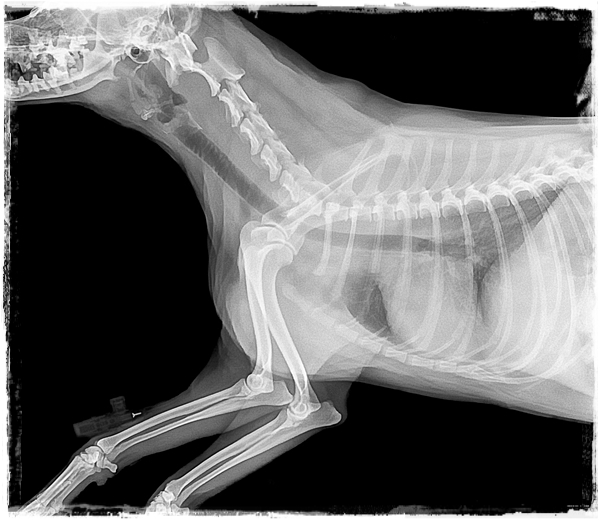

La displasia de cadera es una condición genética que causa el desarrollo anormal de las articulaciones de la cadera.

Incidencia y Estadísticas: La displasia de cadera es común en razas grandes y gigantes, con una prevalencia que varía del 5% al 40% dependiendo de la raza.

Comorbilidad: La displasia de cadera puede llevar a osteoartritis severa y problemas de movilidad a lo largo de la vida del perro.

Tratamientos: El tratamiento puede incluir manejo del dolor con antiinflamatorios no esteroides (AINEs), suplementos nutricionales, fisioterapia y, en casos severos, cirugía correctiva.